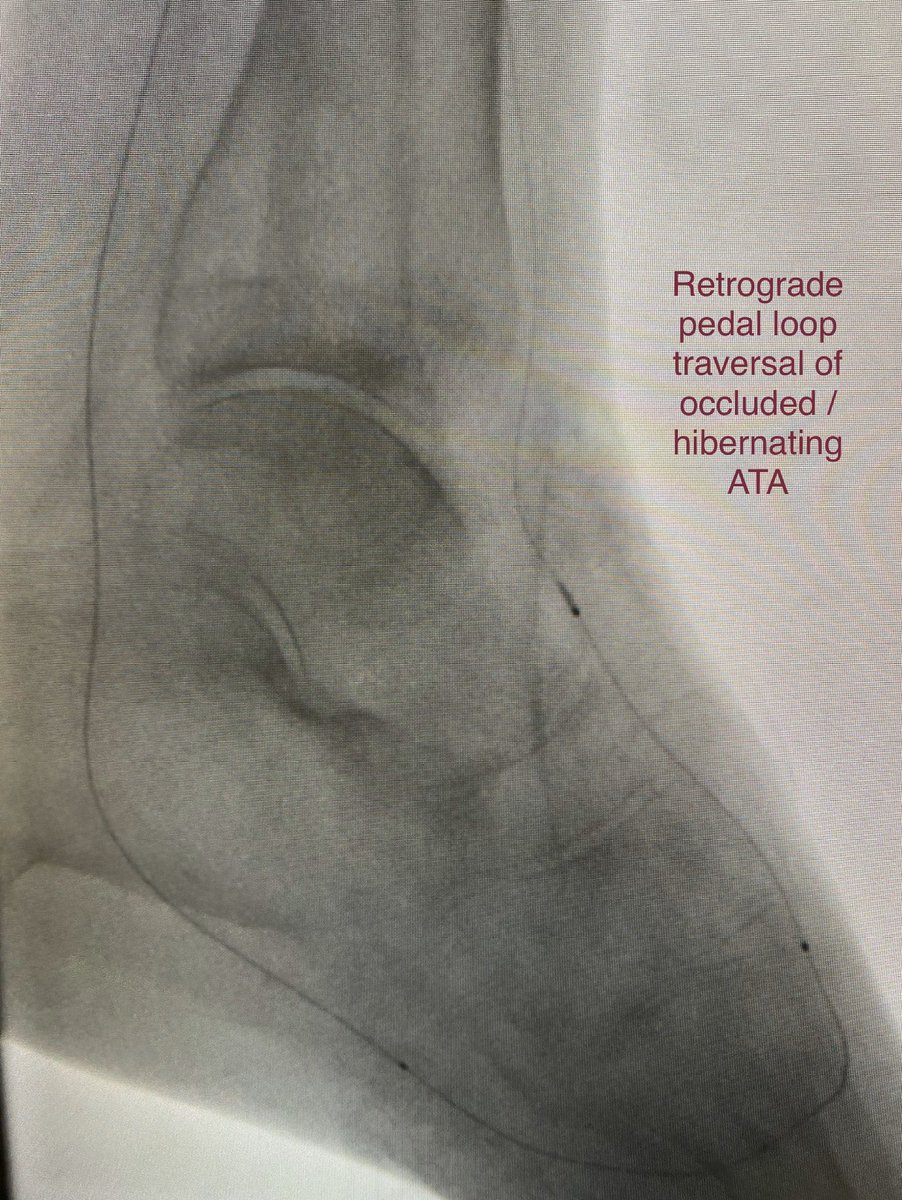

Dorsal foot wound, stent jailing origin of occluded AT, unable to retrograde puncture occluded AT. Pedal loop retrograde traversal of occluded AT to localize its origin followed by antegrade traversal of stent interstices, balloon, stent

@SoFloVIR@OmoKinju@SIRRFSpic.twitter.com/P2QFYbHgG7